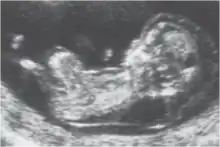

La clarté nucale, petite zone anéchogène (ne renvoyant pas d'écho en échographie) située sur le crâne d'un fœtus humain pendant le premier trimestre de grossesse, permet de dépister certaines anomalies congénitales, en particulier la trisomie 21.

La clarté nucale, comme son nom l’indique, se situe au niveau de la nuque du fœtus. Elle est due à un petit décollement entre la peau et le rachis et correspond à une zone dite anéchogène (c’est-à-dire qui ne renvoie pas d’écho lors de l’examen). Tous les fœtus présentent une clarté nucale au cours du premier trimestre, mais cette clarté disparaît ensuite.